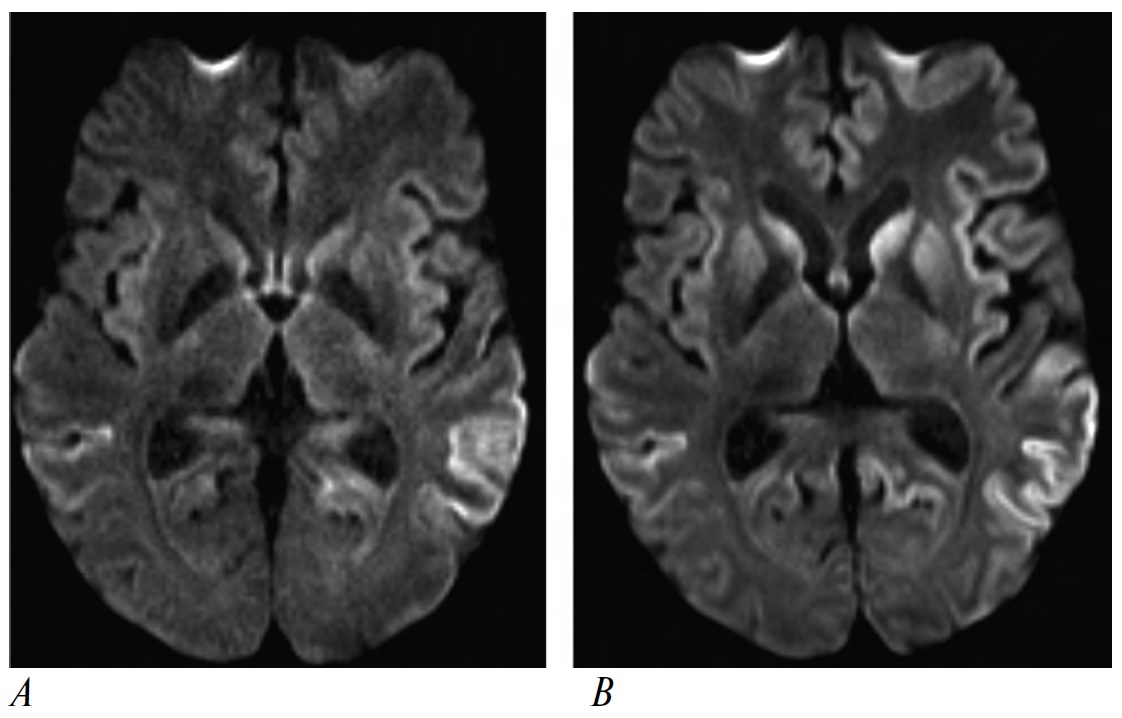

КБС-ЛВД. Женщина, 56 лет. Дебют заболевания в 54 года с постепенного нарастания когнитивных и речевых нарушений, аффективных расстройств, личностных изменений (апатия, инертность, снижение социального интереса). Через полгода появились дрожание в левой руке, изменения аппетита, апраксия в левой руке. Через год после дебюта присоединилась замедленность движений (асимметричная брадикинезия, ригидность, S>D). При осмотре в 56 лет в неврологическом статусе, помимо асимметричного акинетико-ригидного синдрома и апраксии, выявлена дистоническая установка в левой руке. Семейный анамнез не отягощён. При МРТ головного мозга визуализируется асимметричная атрофия лобно-височно-теменных долей, больше справа (рис. 2). При ДНК-диагностике выявлена гетерозиготная мутация в гене GRN. На основании клинической картины и результатов ДНК-диагностики установлен диагноз поведенческого варианта ЛВД. Однако, учитывая наличие ассиметричной ригидности, дистонии и апраксии, её двигательные нарушения могли бы быть классифицированы и как проявления КБС, что хорошо иллюстрирует определённую условность клинических границ между этими фенотипами.

Рис. 2. МРТ головного мозга пациентки с фенотипом КБС в рамках поведенческого варианта ЛВД с выявленной мутацией в гене GRN / Fig. 2. Brain MRI of patient with CBS phenotype as part of behavioral variant of frontotemporal dementia with a mutation in the GRN gene